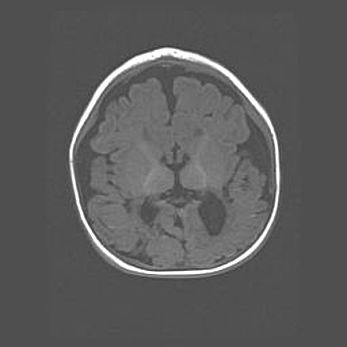

Наружная гидроцефалия с возможной атрофией височных областей.

Возраст: 28 дней

Вес: 3670 г

Пол: мужской

Окружность головы: 38 см

Срок гестации: 40 недель

Гидроцефалия головного мозга у новорожденных – это заболевание, которое характеризуется скоплением избыточного количества спинномозговой жидкости в желудочковой системе головного мозга в результате затруднения её перемещения от места выработки к месту поглощения в кровеносную систему или вследствие нарушения абсорбции. При открытой наружной форме гидроцефалии у новорожденных расширяются и переполняются субарахноидные пространства.

При нормотензивных  формах,  которые,  как  правило,  являются  следствием  перенесенных ишемических  повреждений  паренхимы  мозга,  возможно  сочетание микроцефалии  с нормотензивной гидроцефалией. В основе данных изменений лежит атрофия больших полушарий с преимущественной  локализацией  в  лобно-височных  областях.